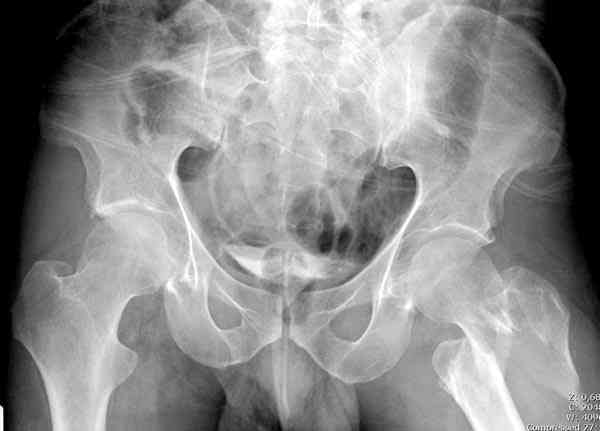

Re: [1/3] Перелом проксимального бедра

Молиборскийй В. 30 Апрель 2006, 06:09

Gamma стержень даже короткий а нагрузку через полтора месяца постепенно

Применили проксимальную Synthes Locking plate, из-за множественных фрагментов посчитали более приемлемым в этом случае (клиника университетская, резиденты должны имет возможность созерцать разные варианты остеосинтеза).

Также старался минимизировать доступ на уровне перелома с субвастус доступом, диафиз фиксирован перкутанно, не стали гонятся за малым вертелом, как смог зафиксировал.

Перелом из четырех фрагментов, не стабильный (лекция Michael R. Baumgaertner, http://www.hwbf.org/ota/bfc/baumg/exp.htm), нужна стабильная фиксация.

Фиксация таких нестабильных чрезвертельных и reverse obliquity субтрохантерик переломов всегда была сложной задачей и ранее использовали Blade Plate. Но многие локальные общие ортопеды, к которым, в основном поступают такие больные, имели трудности с применением импланта, где необходимо было точная калькуляция по введению Blade и поэтому Synthes разработал Proximal Locking plate как альтернативу, где три проксимальные шурупа в разных направлениях создают концепцию угловой стабильности Blade Plate.

Со второго дня движения в суставе, контрольный осмотр через две недели и в зависимости от рентгенологического сращения, дозированную нагрузку с постепенным увеличением начнем через 5-6 недель.